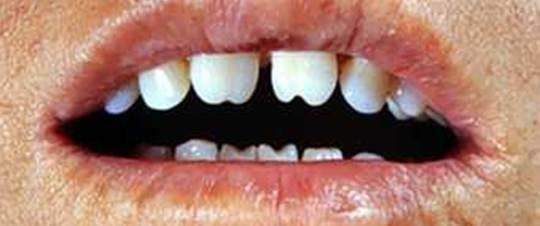

Если зубы располагаются друг от друга на слишком большом расстоянии, то такое состояние называют диастемой. Дефект чаще наблюдается между передними зубами.

Диастема — щель между зубами

Данная патология представляет собой промежуток между фронтальными резцами. В большинстве случаев проблема возникает на верхней челюсти.

Диастема бывает настоящей и ненастоящей. Первая появляется, как результат попадания волокон соединительной ткани уздечки губы в срединный шов. Вторая возникает во время смены зубов, проходит самостоятельно по окончании выхода наружу клыков и боковых резцов.